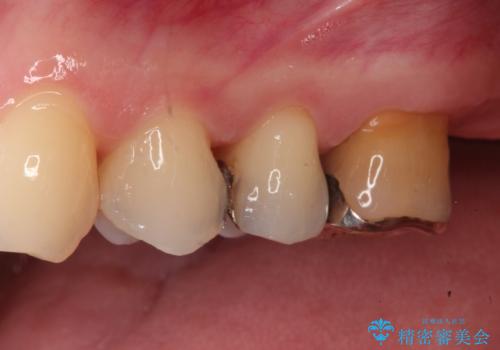

装着したセラミックインレーは、隣り合う天然歯と見分けがつかないほど自然な色調と透明感を再現しています。また、セラミックはプラーク(歯垢)が付着しにくく、適合性が非常に高いため、二次的な虫歯の予防にも大きく貢献します。

お口を開けた際に目立っていた銀色の部分が解消され、清潔感のある明るい口元になりました。金属アレルギーの心配もなく、健康的で美しい状態を長期的に維持することが可能です。